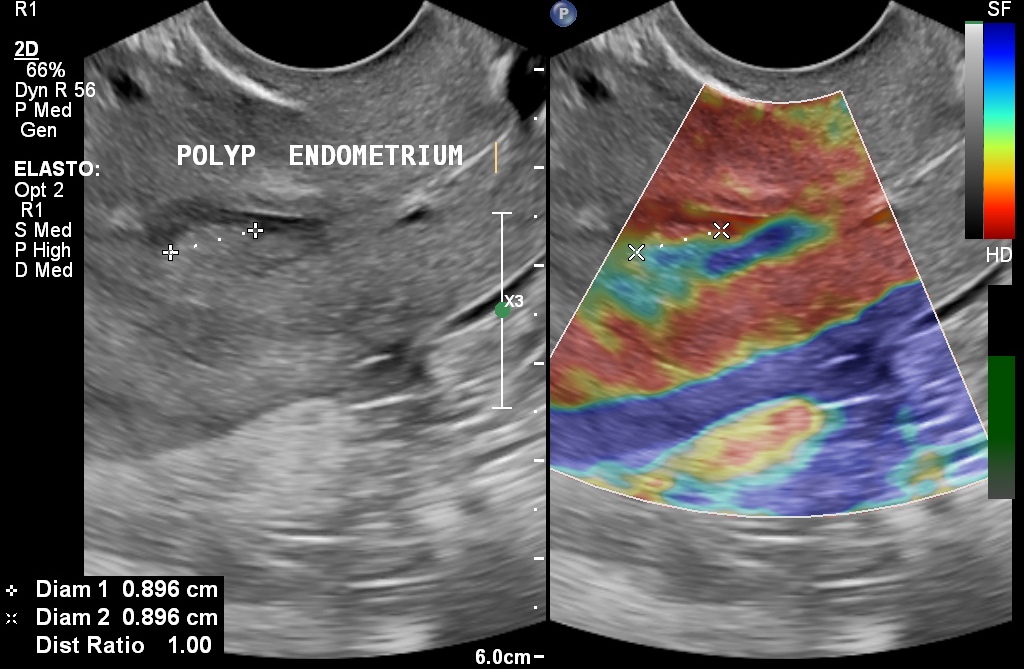

Pelvic Ultrasound

This is commonly required for a variety of indications including menstrual irregularities, irregular or excessive bleeding, after D&C, pelvic pain etc. Both trans-abdominal and transvaginal approaches are ofetn required.